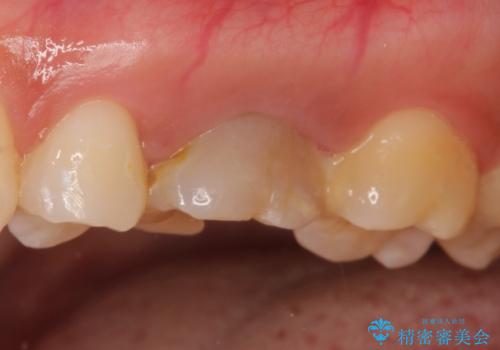

再根管治療後、歯周外科を行い、オールセラミッククラウンにて修復処置を行っております。